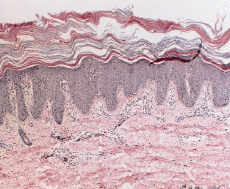

Un varón de 9 meses de edad fue remitido a nuestro Servicio en 1983 por presentar pocos meses después de su nacimiento unas placas rojizas y descamativas en la cara, extremidades y tronco que fueron intensificándose, acompañándose de afectación palmar sin otra sintomatologia acompañante. No existían antecedentes personales ni familiares de interés. En la exploración se apreciaban placas eritematoqueratósicas, bien delimitadas, simétricas y fijas, en ambas mejillas, en extremidades superiores, especialmente a lo largo de la zona de extensión, al igual que en extremidades inferiores (Fig. 1) y en parte del tronco. Presentaba, además, una leve queratodermia palmar. Se practicó analítica, incluyendo hemograma y bioquímica sanguínea, que resultaron dentro de los límites de la normalidad. Se realizaron dos biopsias de brazo y antebrazo que mostraron acantosis psoriasiforme con atrofia de la granulosa y capas alternantes horizontalmente de orto y paraqueratosis. Se veían ocasionales queratinocitos eosinófilos. En la dermis superficial había un ligero infiltrado linfohistiocitario perivascular (Fig. 2). Entre 1984 y 1993 se administró tratamiento con etretinato por vía oral a dosis de entre 0,5 y 1,5 mg/kg/día, con evidente mejoría en sus lesiones cutáneas. Las épocas de descanso del tratamiento se acompañaron de empeoramiento o reaparición de sus lesiones. La tolerancia clínica y analítica al tratamiento fue buena a lo largo de este período. En julio de 1993 el paciente dejó de seguir voluntariamente revisiones en nuestro Servicio.

FIG. 2.--Biopsia cutánea tomada en el primer año de vida. Se aprecia acantosis psoriasiforme con atrofia de la granulosa y una córnea engrosada en la que alternan capas horizontales ortoqueratosis (azules) y paraqueratósicas (rojas). Leve infiltrado linfocitario en algunas papilas.